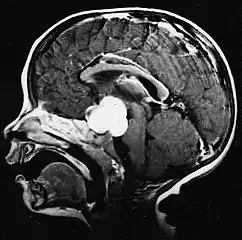

Sagittal T1-weighted MRI showing a well-circumscribed hypointense mass in the tectum (presumably a tectal plate glioma). These lesions are a distinct subset of pilocytic astrocytoma which present with hydrocephalus typically in 6 to 10 year-olds and are rarely progressive lesions. When imaging is characteristic, a biopsy is usually not performed because of the risks to adjacent structures, often shunting to relieve intracranial pressure is the only treatment required.